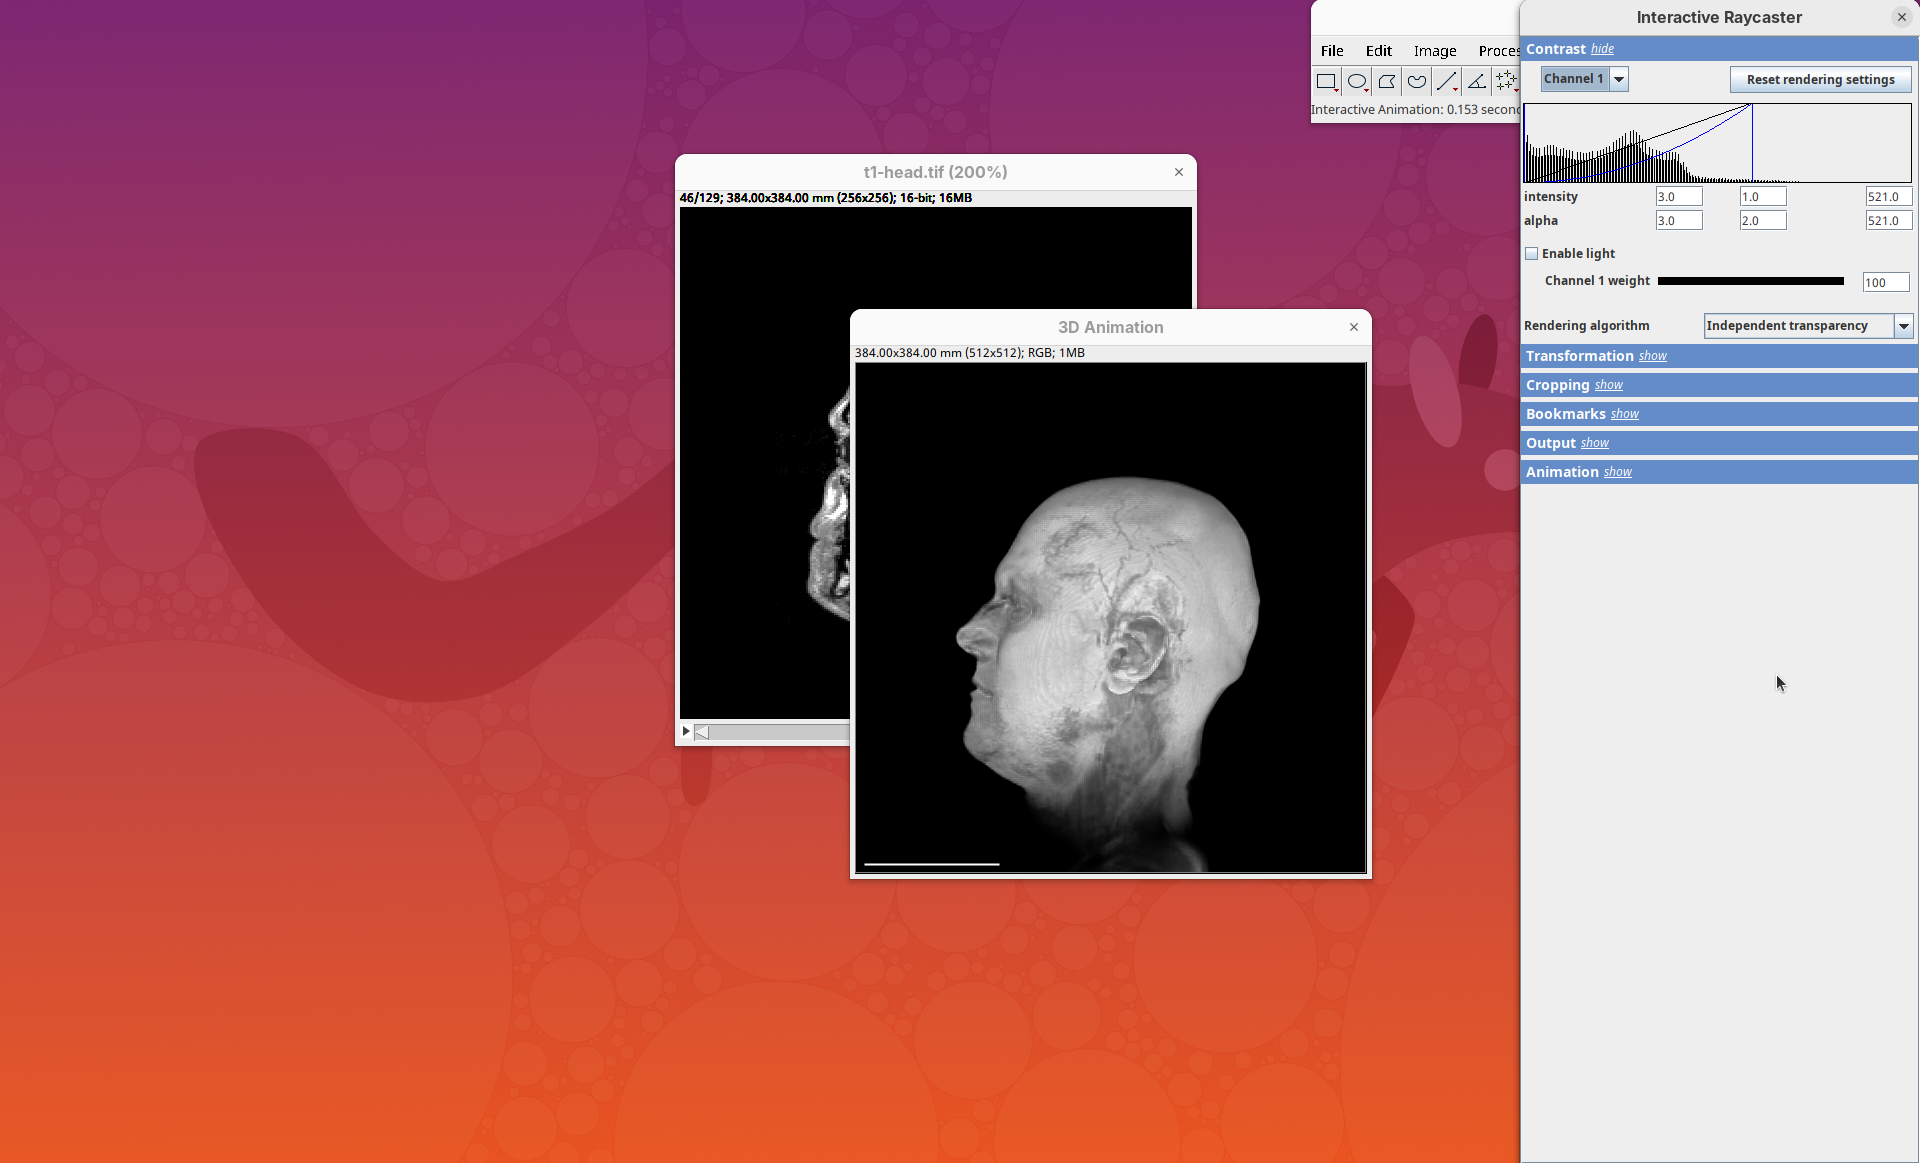

Two new windows will open: 3D Animation with the initial rendering of the data and Interactive Raycaster with all the fields to control the rendering parameters.

Contrast

The Contrast section shows a histogram of pixel intensities of the image for each channel, which we can choose using the dropdown menu. We can set the minimum, gamma, and maximum values for the intensity and alpha (transparency) properties of each pixel. The weight option controls the general opacity of the channel (0=invisible, 100=visible). There’s also more advanced options like lighting and rendering algorithm which we’ll simply use the default states as they are usually good for most use cases.

Adjusting the intensity and alpha values is the most impactful way to improve the 3D rendering. With the intensity setting we can define which pixel value in the image corresponds to total black (minimum) and which corresponds to total white. It’s the same as in the standard Brightness & Contrast tool. By default, 3Dscript will load these values from the original stack. In this case, it loaded min=3 and max=521.

Transformation

The transformation menu has controls for rotating, translating, and scaling the sample. We can either add values or manually interact with the 3D Animation window to reorient the sample. Let’s try the latter.